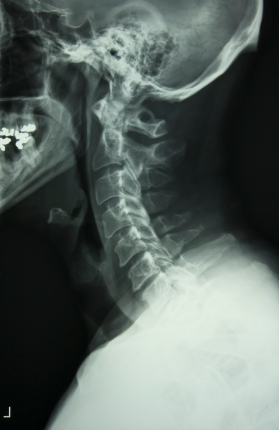

- Whiplash injuries: All it takes is the sudden movement of the neck to cause a whiplash injury, which is especially common in rear-end collisions.

- Herniations: We will make sure you see a doctor who can help you recover and demonstrate the cause of your injury in court, if needed.